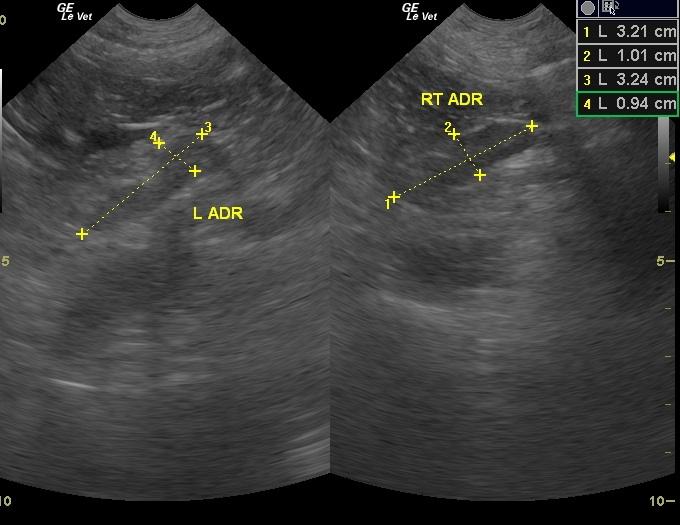

A 13 year old, SF mixed breed dog was presented for polyuria, polydypsia, and loss of fur. On physical examination, she had a pot-bellied appearance. Urinalysis revealed 2+ proteinuria and positive microalbuminuria. Elevated ALP activity and hyperlipasemia were evident on blood chemistry. ACTH stimulation test showed normal baseline cortisol level with an elevated level post ACTH. Adrenal panel revealed increased baseline androstenedione with elevated level post ACTH, increased baseline estradiol with normal value post ACTH, and normal baseline progesterone with elevated level post ACTH. On dexamethasone suppression test, basal cortisol was 2.6 and the 8 hour value was 8.6. T4 was low.